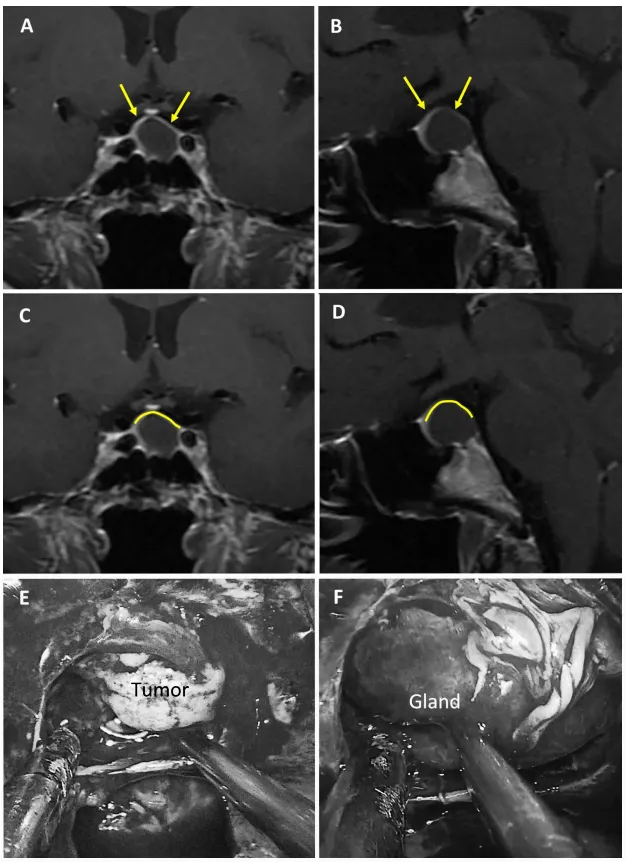

1強韌型鞍隔屏障案例

圖2

圖2:75歲女性無功能大腺瘤患者。a、b術(shù)前MRI:黃色箭頭指示厚度大于1毫米的強化屏障區(qū)。c、d術(shù)前MRI:黃色標記線標示強韌屏障位置。e、f術(shù)中圖像:可見由垂體腺構(gòu)成的屏障結(jié)構(gòu)。